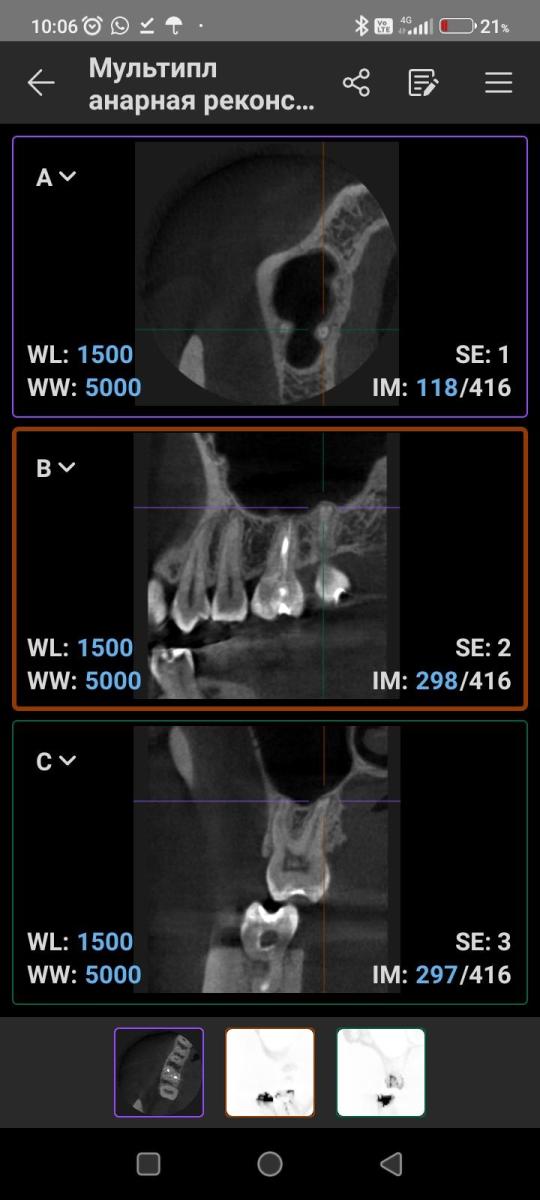

Что может означать затемнение на верхушке корней 17 зуба? Есть ли дентикли в пульпе? Есть постоянная не острая болезненность по ходу верхнечелюстной ветви. Может ли источником боли быть 17 зуб?

"Что может означать затемнение на верхушке корней 17 зуба?"

"Есть ли дентикли в пульпе?"

"Может ли источником боли быть 17 зуб?"